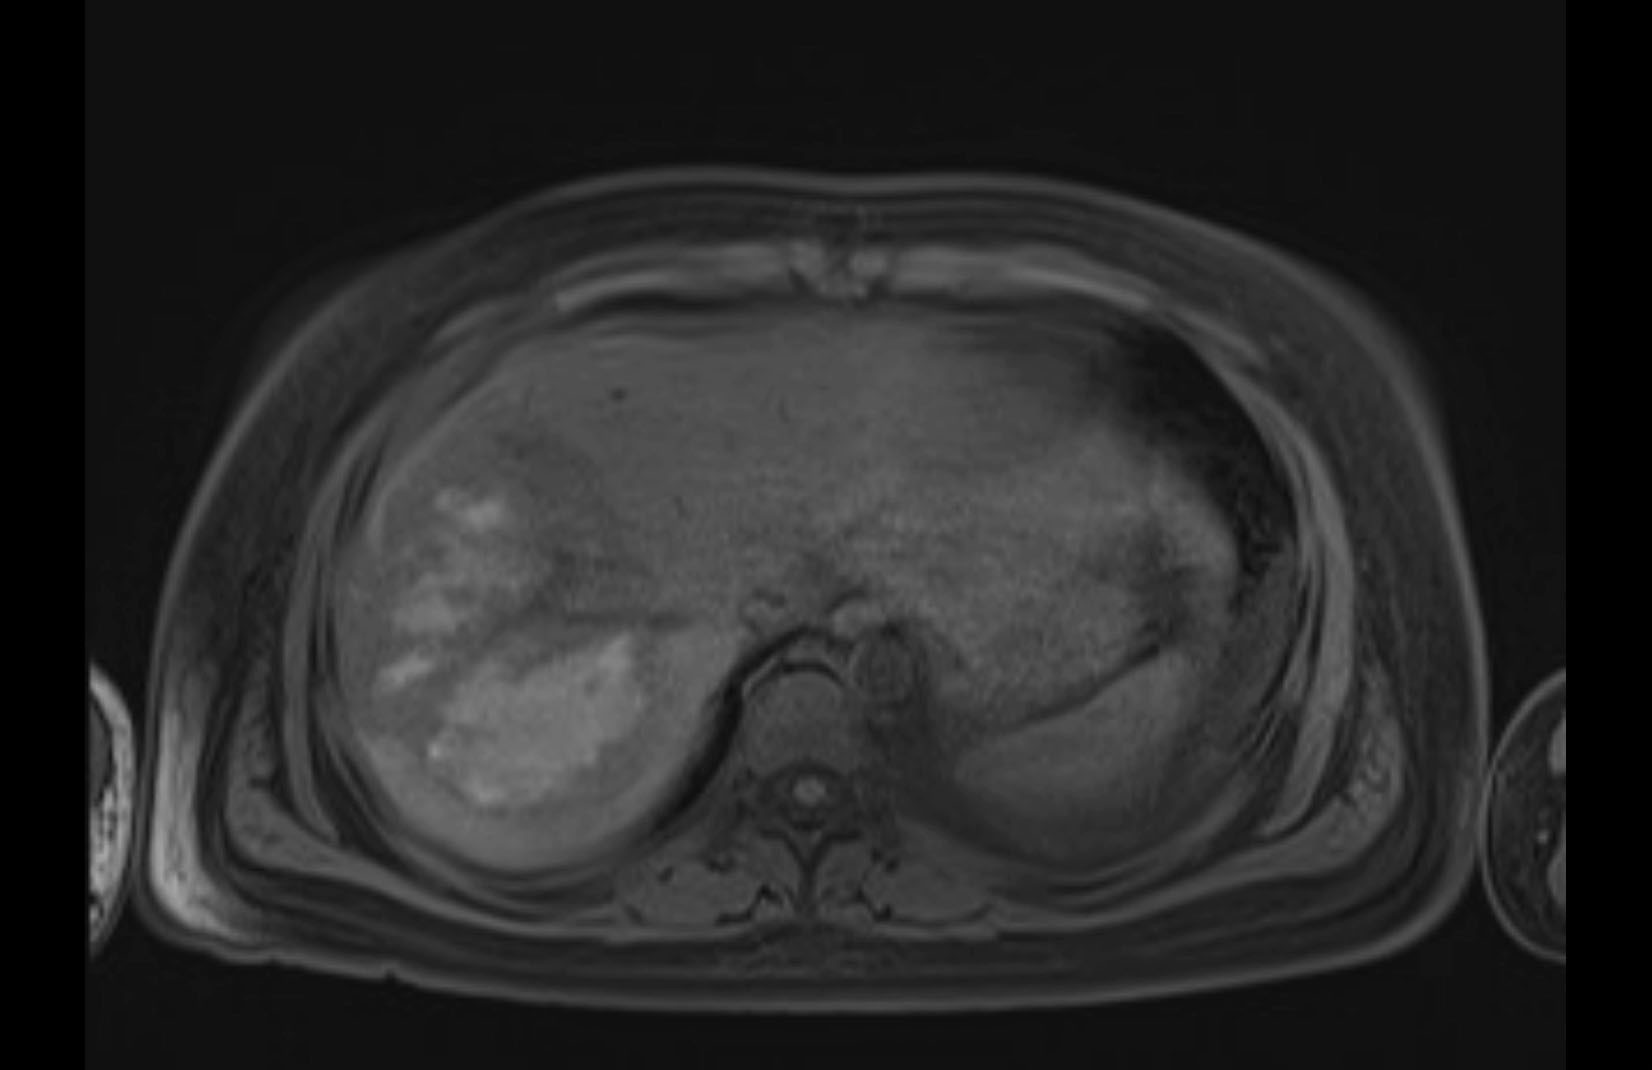

MRI T1